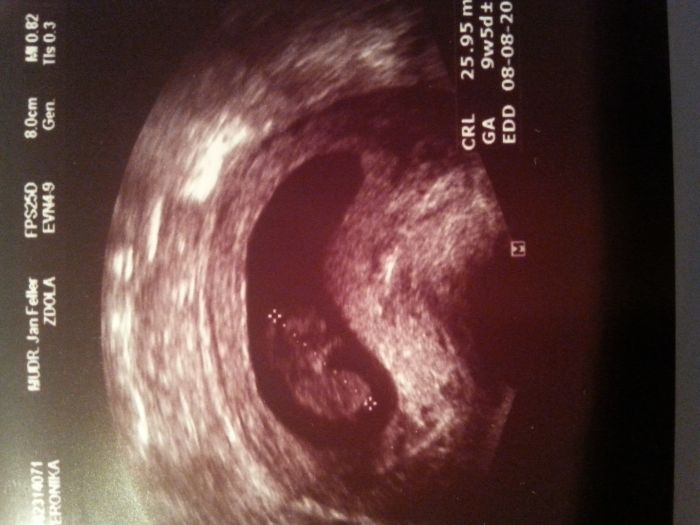

Nestíhám moc dočítat, ale postřehla jsem, že se Tery povedl ten UTZ - tak to gratuluju! Krásný obrázek a krásný zážitek :) Hlavně, že to takhle hezky dopadlo :)

Jíťo však já nelituju. Ani maličko. Člověk vyhodí peníze za jiné zbytečnosti. Bylo to fakt super. A když bych si tady mohla platit normální pojištění, vyjde mě na cca 6tis. měsíčně. Takže to vyšlo ještě dobře. Čekali jsme vyšší částku. Jediné co mě nakonec trošku mrzelo, že kdyby jsme šli vlastně AŽ příští týden, udělali by nám i ten screening, za který chcou jen o něco málo víc než v ČR (což mě překvapilo), jenže jsme vlastně ani nevěděli stáří těhotenství. Ale nemá smysl si to vyčítat, protože posledních pár dní jsem měla čím dál větší strach, že ještě nemáme nic potvrzeno, tak jestli je to vše ok. Navíc poslední dva dny se cítím fakt supr. Ale říkali jsme, že budeme řešit vše jak to bude postupně přicházet a už se stalo. Takže to tak prostě je a díky bohu je vše v pořádku